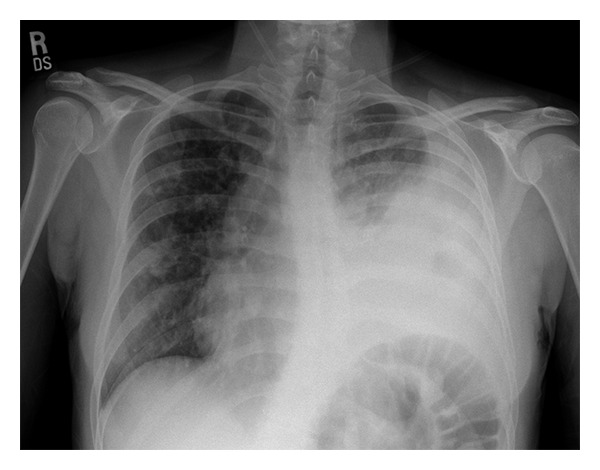

Input 3: What is seen in the X-ray and what should be done?

Image: